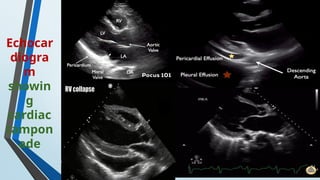

Echocar

diogra

m

showin

g

cardiac

tampon

ade